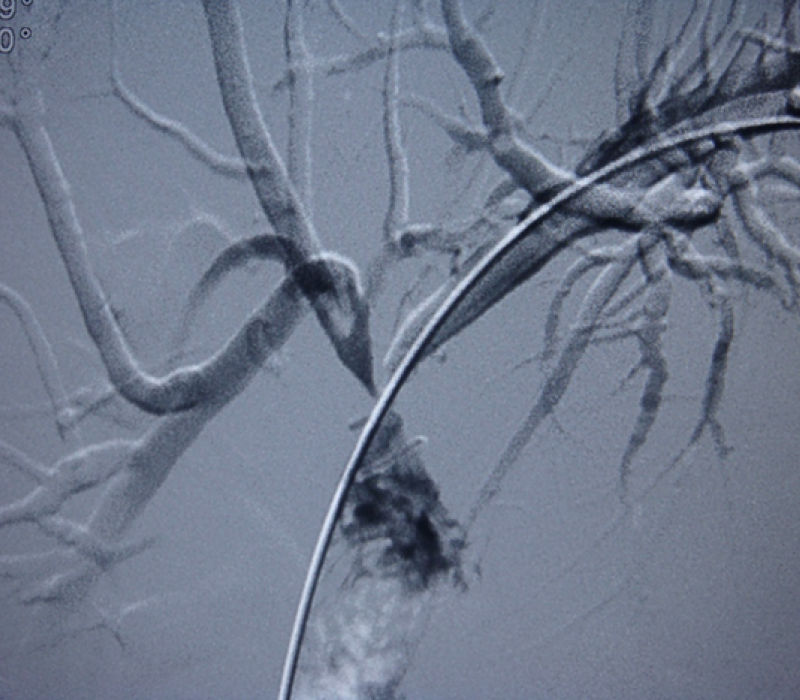

Percutaneous biliary drainage techniques

Obstructive jaundice and bile leaks are indications for percutaneous biliary interventions. Uncomplicated obstructive jaundice is not an emergency, while septic cholangitis needs urgent intervention.

Since the first report of the opacification of the biliary system by percutaneous direct puncture of the gallbladder in 1921, biliary interventions have evolved a great deal becoming readily available in most hospital settings.

The incidence of open and laparoscopic common bile duct exploration for choledocholithiasis has remarkably declined during the last 2 decades. Endoscopic and percutaneous treatment options provide a minimally invasive solution to even complex biliary lithiasis cases.